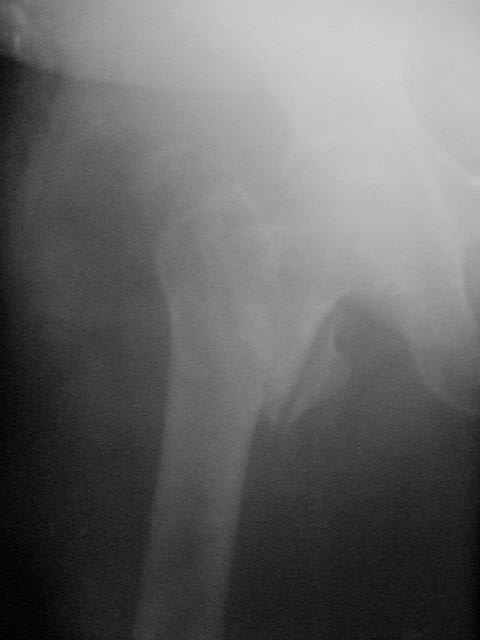

> Здравствуйте коллеги ! Прооперировали женщину 72 лет с Диагнозом: Чрезвертельный перелом

> левого бедра. Первый раз поставили PFN A (SYNTHES) см R-gr.

Присоединяюсь. Хотя посмотреть бы вторую проекцию.

И по фасу - шеечый винт можно бы и подлиннее.

Да? Качество рентгенограмм конечно неочень, но ведь это нестабильный перелом 31.А2.2, не так ли?

> нестабильный перелом 31.А2.2, не так ли?

Ну, после помещения туда такого гвоздя даже без дистального винта заметной нестабильности уже не остается ;-)

Александр упомянул, что выбранный шеечный винт коротковат, и именно поэтому я бы не советовал давать полную нагрузку на оперированную ногу (насколько это возможно у 72 летней больной)

-Субкапитальная зона шейки -слабое место и поэтому, если проведенный винт расположен именно в этой зоне, а не проведён дальше в головку, то есть опасность его миграции: при нагрузке создается опрокидывающий момент и винт разрушает верхний отдел шейки. При правильно выбранном размере винта нагрузку можно начинать сразу, критерий величины нагрузки - болевые ощущения.

Боковая проекция нужна всегда, иногда послеоперационные снимки преподносят неожиданные сюрпризы:-(( даже при использовании ЭОПа интраоперационно.